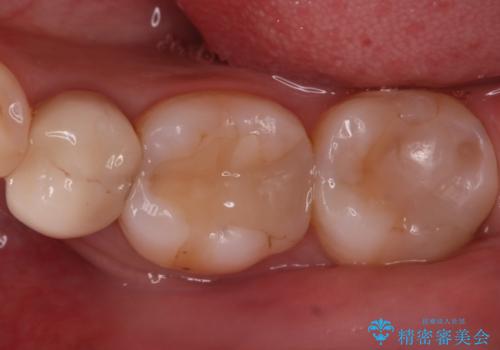

- 奥歯に虫歯があると言われて治療された患者様です。

何度か同じ歯に保険治療で治したそうですが、欠けたり再度う蝕になってしまった経験から自費治療を希望され、丈夫でキレイなセラミッククラウンにて治療いたしました。

噛み合わせや食べ物の詰まりなどは問題なく、経過良好とのことで満足いただけました。